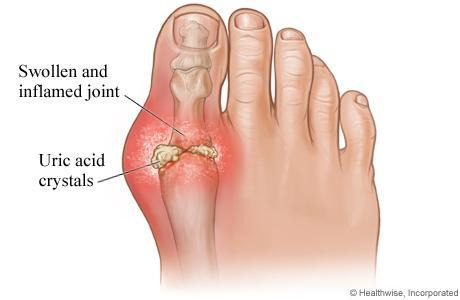

11. 통풍 (Gout)

- 원인: 요산 결정이 발 관절에 쌓이며 염증 유발.

- 특징: 엄지발가락 관절 주변 심한 통증과 붓기.

- 위험 요인: 고퓨린 식단, 음주, 비만.

- 대처법: 식이조절, 약물치료.